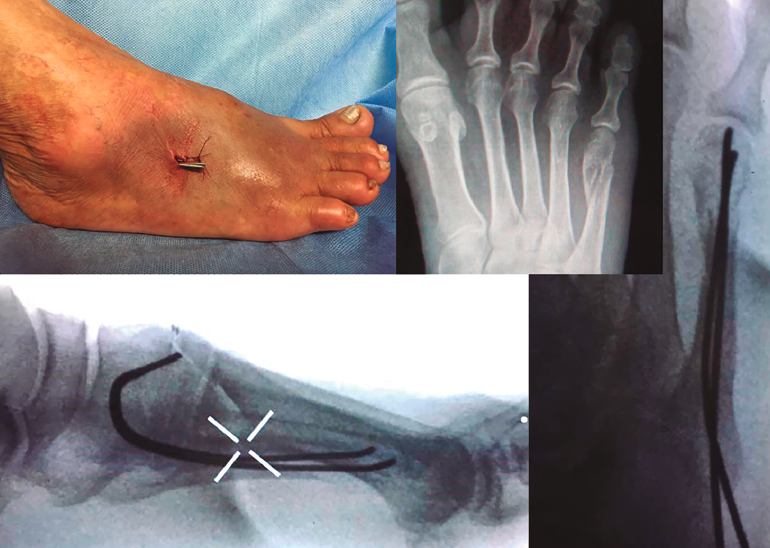

En las Figuras 3 y 4 se presentan los resultados postoperatorios de los pacientes incluidos en nuestro estudio.

Figura 4. Octavo paciente objeto de nuestro estudio, femenino, de 60 años, quien sufre fractura en 5.º metatarsiano por traumatismo indirecto en caída por motocicleta. En sentido horario empezando arriba a la izquierda: imagen fluoroscópica lateral al finalizar el procedimiento quirúrgico, radiografía preoperatoria, fijación interna anterógrada con doble alambre de Kirschner de 1,5 mm y aspecto del pie al finalizar el procedimiento quirúrgico.